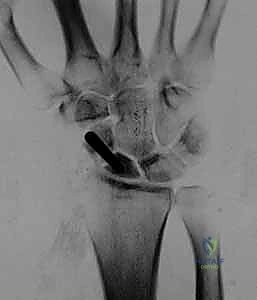

- الأشعة السينية الرقمية (Digital X-rays): بأوضاع متعددة (AP, Lateral, Scaphoid view) لتقييم زوايا العظام ودرجة الانهيار.

- الأشعة المقطعية (CT Scan): وهي المعيار الذهبي لتقييم حجم العظم المتآكل بدقة ثلاثية الأبعاد، وتحديد مدى الخشونة في المفاصل المحيطة.